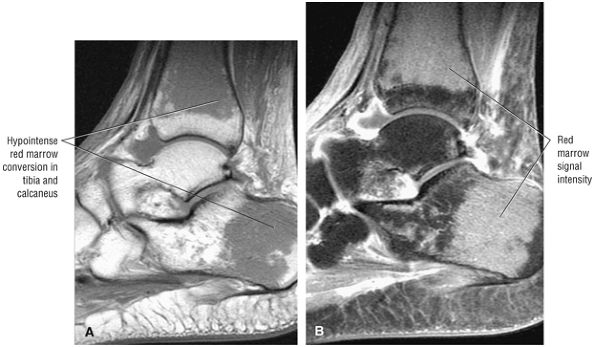

lateral) × 8 mm (anterior to posterior) fragment of bone within the osteochondral bed (Fig. 5.57C, D). There is bone marrow edema associated with the osteochondral lesion (Fig. 5.57E). The bone marrow edema is in a 1-cm area. There is interruption of the subchondral plate in the area of the osteochondral lesion (Fig. 5.57F).

Medial osteochondral talar dome lesion. There is a fragment of osseous tissue within the osteochondral bed that may be attached by synovium. The fragment measures 8 mm anterior to posterior and 3 mm medial to lateral. This correlates with a stage III osteochondral lesion. There is associated bone marrow edema of 10 mm and subchondral sclerosis. There is irregularity of the overlying subchondral plate. There are also mild cystic changes in the adjacent portion of the talus, although no fluid is directly undermining the osteochondral lesion itself.

Anterior osseous impingement of the ankle with spurring of the anterior aspect of the tibiotalar joint and bone marrow edema demonstrated in the anterior distal tibia

Chronic thickening of the anterior talofibular ligament without disruption